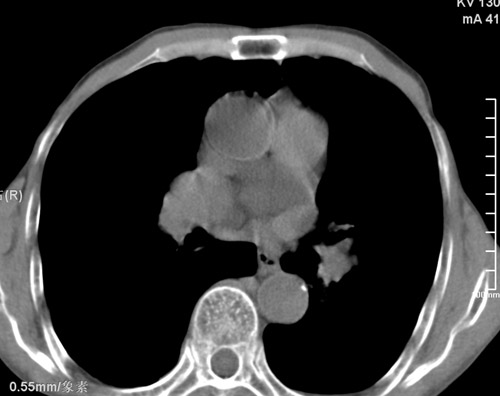

标题: CT17529:男 76 胸背部不适半月 胸透支气管炎 行CT检查 [打印本页]

标题: CT17529:男 76 胸背部不适半月 胸透支气管炎 行CT检查

意见 老年肺 少许炎症 肺大泡 右肺门略大 但支气管通畅  请各位高手指教如何下意见

支持楼主意见,右肺门略大,可能为肺动脉增粗.

慢支肺气肿,肺动脉高压.